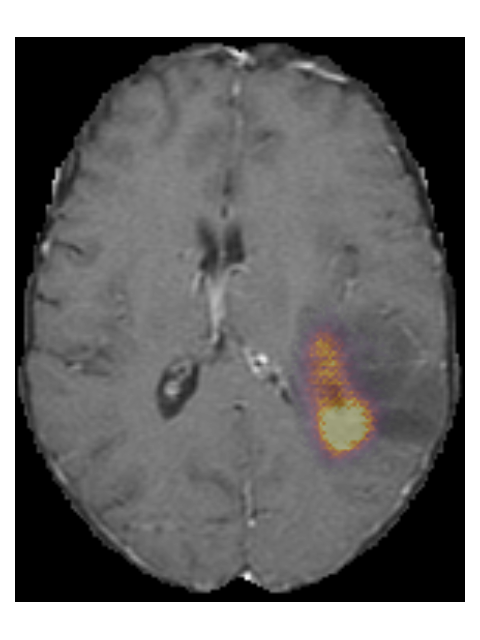

To provide insight into the behavior of our model we created saliency maps, which show which parts of the scans contributed the most to the prediction. These saliency maps are shown in Figure 6 for two example patients from the test set. It can be seen that for the LGG the network focused on a bright rim in the T2w-FLAIR scan, whereas for the HGG it focused on the enhancement in the post-contrast T1w scan. To aid further interpretation, we provide visualizations of selected filter outputs in the network in Appendix D, which also show that the network focuses on the tumor, and these filters seem to recognize specific imaging features such as the contrast enhancement and T2w-FLAIR brightness.